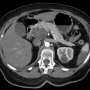

Irene Blair, a patient from Chicago, was facing a grim prognosis of only six to eight months remaining in June 2023. Diagnosed less than a year ago, her cancer had aggressively progressed, leaving her and her family desperate for options. However, the recent development surrounding this novel treatment offers a glimmer of hope in what is often deemed one of the deadliest forms of cancer.

The FDA has granted fast-track designation for this innovative therapy, which has demonstrated the potential to double survival rates in early clinical trials involving over 500 participants. The results reveal that patients like Blair can now expect to live longer and with a better quality of life, raising optimism among medical professionals and families alike.